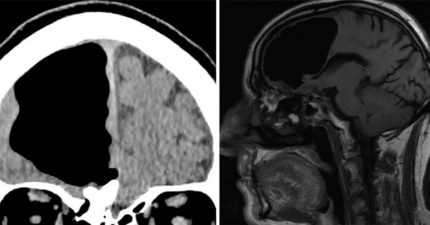

男子被驗出「巨大腦洞」,「半個大腦不見了」但仍跟我們一樣正常!醫生這樣解釋

March 21, 2018